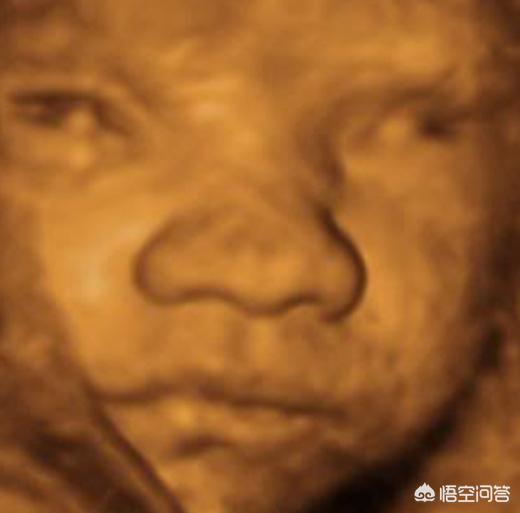

怀孕28周左右:宝宝可以睁眼、闭眼并且四处转动眼睛了 。 我们可以想象这就是宝宝在妈妈肚子里面“练习”转眼睛呢 。

----听说以前小孩子生下好几天才睁开眼 , 现在生下来就能睁开眼 , 为什么?//---- http:// //